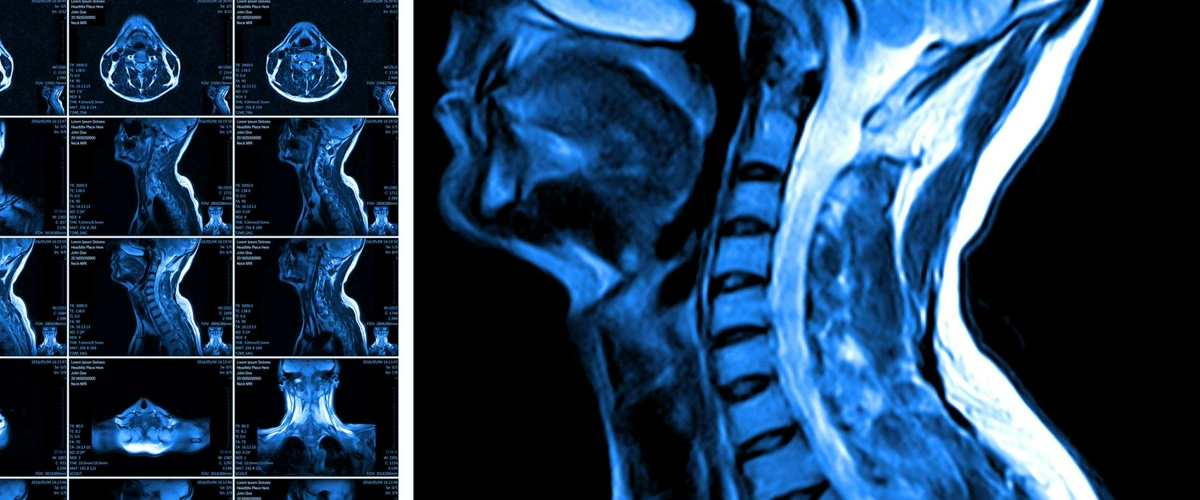

Перепрограммирование стволовых клеток: прорыв в лечении травм спинного мозга

Представьте себе супермагистраль, которая связывает ваш мозг с каждой мышцей тела. Это спинной мозг. Но травма на этом пути — и связь обрывается, приводя к параличу. Виной всему не только порванные «провода»-нервы, но и гибель особых клеток-изоляторов — олигодендроцитов. Без них электрические сигналы просто рассеиваются.